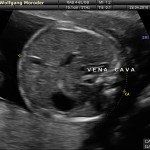

L’ecografia è una tecnica che consente di vedere gli organi del nostro corpo con l’utilizzo di onde sonore ad alta frequenza (ultrasuoni, non udibili dall’orecchio umano) che attraversano i tessuti. La sonda ecografica invia impulsi di onde sonore nel corpo. Quando le onde sonore arrivano al feto mandano degli echi: tali echi (o onde di ritorno) sono trasformati in immagini sul monitor dell’ecografo. Con l’ecografia è quindi possibile osservare in modo dettagliato il feto.

A fianco alla più tradizionale ecografia eseguita per via transaddominale, risulta particolarmente utile nell’esame ecografico ostetrico e ginecologico la via di accesso transvaginale.

Con questa metodica, utilizzando delle sonde ecografiche appositamente predisposte (per forma e dimensione, e per frequenza di emissione degli ultrasuoni) è possibile controllare la gravidanza nel primo trimestre con una qualità e definizione d’ immagine nettamente superiori a quanto possibile per via transaddominale.

Per eseguire l’ecografia transvaginale non è richiesta la vescica piena, diversamente rispetto a quanto richiesto per l’ecografia transaddominale. L’approccio transvaginale consente di aggirare l’ostacolo dovuto ad un aumentato spessore della parete addominale (obesità). In questi casi infatti la qualità d’ immagine in caso di ecografia transaddominale viene fortemente penalizzata dall’eccessivo spessore del pannicolo adiposo addominale.

Successivamente può risultare utile il ricorso all’ ecografia transvaginale nei casi in cui si sospettino delle modificazioni precoci (raccorciamento) del collo dell’utero, come potrebbe verificarsi nei casi di minaccia d’ aborto o di parto pretermine.

In questi casi infatti è possibile con l’ ecografia misurare con precisione la lunghezza del collo uterino. In questi casi inoltre l’ ecografia può anche evidenziare un’ iniziale dilatazione dell’ orifizio uterino interno. Tali modificazioni del collo dell’ utero, valutabili con accuratezza solo con l’ ecografia transvaginale, hanno una grande importanza nel considerare un eventuale rischio di parto pre-termine.